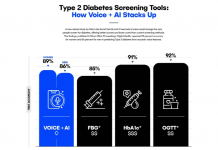

AI가 10초 음성으로 당뇨병 진단…”정확도 86% 이상”

스마트폰에 녹음된 10초 정도의 목소리만으로 제2형 당뇨병 여부를..